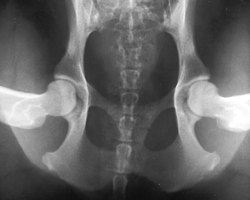

3. gestreckte Hüfte

Die Hintergliedmaße des Patienten sind gestreckt. PennHIP nutzt diese Aufnahme, um Anzeichen einer Arthrose im Sinne einer degenerativen Gelenkserkrankung zu identifizieren. Traditionelle HD-Untersuchungen werden oftmals nur in dieser Position durchgeführt. Bei einem klassischen Verfahren würde dieser Patient gut abschneiden, da in der gestreckten Aufnahme kein Hinweis auf eine Arthrose oder auch Lockerheit der Hüfte zu finden ist. In der 1. Distraktions Aufnahme hingegen sieht man, dass die Hüfte nicht den straffen Eindruck vermittelt, den sie in der 3. gestreckten Aufnahme zu erwecken versucht. Die Hüfte ist "locker". Somit steigt die Gefahr einer Hüftgelenksdysplasie, in vielen Studien nachgewiesen, deutlich an. Dieser Hund wird mit großer Wahrscheinlichkeit in seinem weiteren Leben eine Arthrose im Bereich des Hüftgelenkes entwickeln.